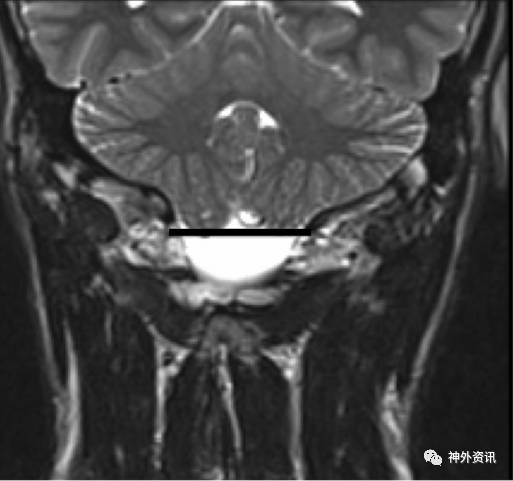

作者回顾性分析50例诊断为Chiari I型畸形的小儿患者,年龄2-21岁,平均9.3岁。在MRI矢状位和冠状位上测量和比较小脑扁桃体下疝情况(图1、2、3、4)。

图1. MRI冠状位图像,水平线画在枕骨大孔的最低点;见小脑扁桃体下疝入枕骨大孔。

50例患儿中,48例在MRI冠状位发现小脑扁桃体不对称,左侧扁桃体下疝最大值为20.9毫米,右侧扁桃体下疝最大值为17.4毫米。MRI矢状位上,小脑扁桃体下疝范围从5-27.4毫米不等。5例(10%)患儿在MRI冠状位发现双侧小脑扁桃体下疝至枕骨大孔下长度小于3毫米,19例(38%)在冠状位上一侧小脑扁桃体下疝小于3毫米。但在MRI矢状位上扁桃体下移都超过3毫米,而每例患儿在MRI正中矢状位上的小脑扁桃体下疝均大于3毫米。作者依据测量的结果认为,Chiari I型畸形常常是不对称的小脑扁桃体下疝。如果仅在MRI正中矢状位上测量,小脑扁桃体下疝可能会造成误诊。因此,不应采用单一的MRI矢状位成像诊断Chiari I型畸形小脑扁桃体下疝的程度。